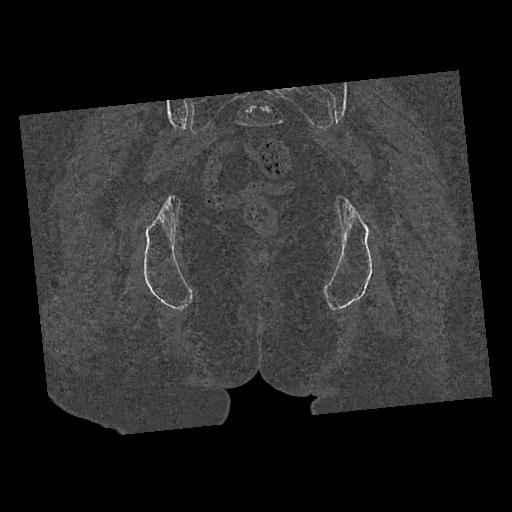

100703 1/27 両股正面+軸 1/29 両股正面+軸 94歳女性 パンソンロン